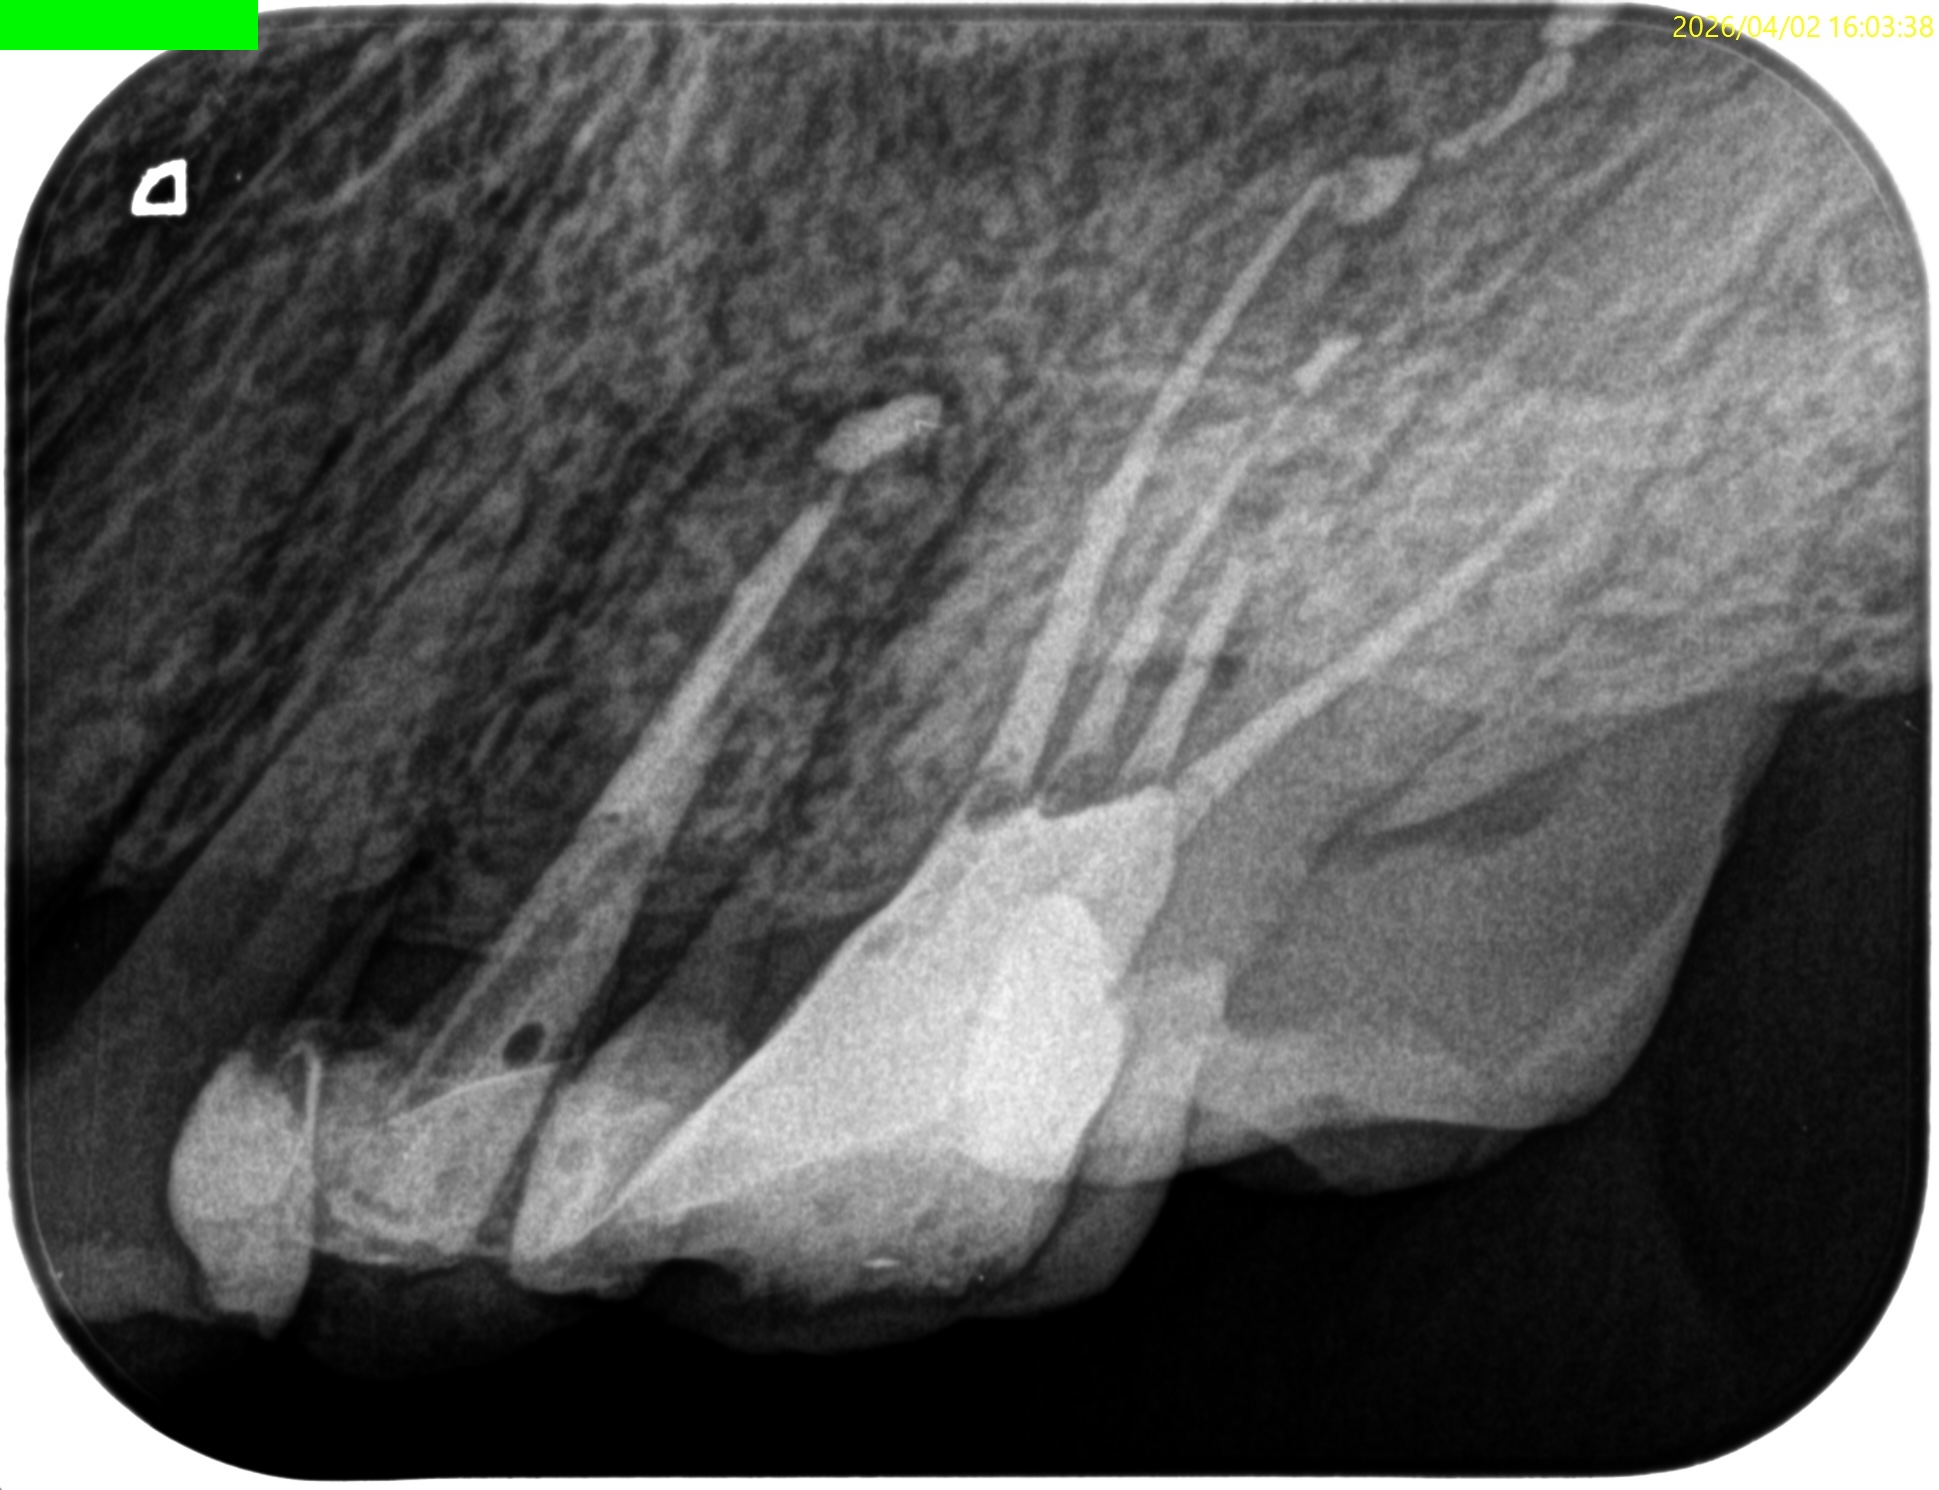

Pre-op Endo test(2026.4.2)

このPA2枚でみても、東京の歯科医院の担当者は根管口さえ発見していないという臨床的事実がわかる。

ということで、主訴の#14から再根管治療を行い、残された時間で#13を行うことになった。

その際は、

MB1

MB2

DB

P

#13

おおよその作業長が類推できる。

が、いずれにしてもこの治療での最大のポイントになるのはMB2がどこにあるか?である。

MB2の根尖部にはCBCTで根尖病変があるからだ。

#14 Re-RCT(2026.4.2)

#13 Re-RCT(2026.4.2)

ということで、術後にPA, CBCTを撮影した。

#14

#14 Pは外部へBC sealerが溢出したが、